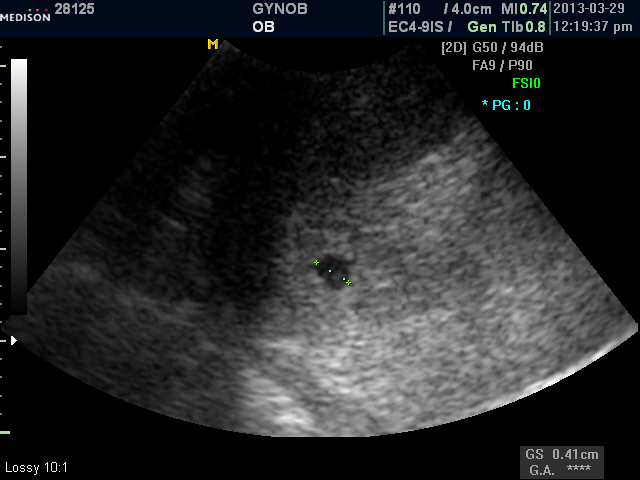

저 역시 기쁘고 왠지 초음파 사진을 보는데 뭉클해지네요 ..

유난히 아기집도 예쁘게 보입니다

아기 집 보인다는 소식을 건너 듣고, 어찌나 기쁘던지!

이제 예쁜아기집도 보이니, 아침마다 뵙는 얼굴에 조금 더 웃으셔도 좋을것 같아요.